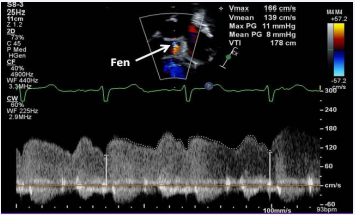

Figure 33 Selected video frame with Doppler sampling across the fenestration (Fen) demonstrating a mean gradient of 8 mmHg [69].

Figure 33: Selected video frame with Doppler sampling across the fenestration (Fen) demonstrating a mean gradient of 8 mmHg [69].

Stage IIIB: During the Stage IIIB, the fenestration is occluded (Figures 35) by transcatheter methods [32,46,82,85-87], usually 6 to 12 months following Stage IIIA Fontan. In the past, most devices used to occlude ASDs [46,87-87], were used for this purpose, but now, Amplatzer Septal Occluders are the most frequently used devices to accomplish such closures. If there are any other residual shunts, they are also occluded by device closure.

Figure 32 Selected video frames (A and B) from an apical four chamber view focusing on the conduit (C) (A) and with color flow imaging (B) demonstrating fenestration (FEN). ATV, atretic tricuspid valve; LV, left ventricle [69].

Figure 32: Selected video frames (A and B) from an apical four chamber view focusing on the conduit (C) (A) and with color flow imaging (B) demonstrating fenestration (FEN). ATV, atretic tricuspid valve; LV, left ventricle [69].